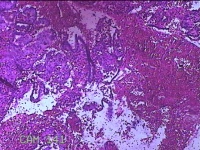

性别

女

年龄

46岁

临床诊断

异常子宫出血

一般病史

阴道流血伴血块6天。

标本名称

宫腔内组织

大体所见

灰白暗红色不规则碎组织2.5x2x0.7cm一堆。

图3